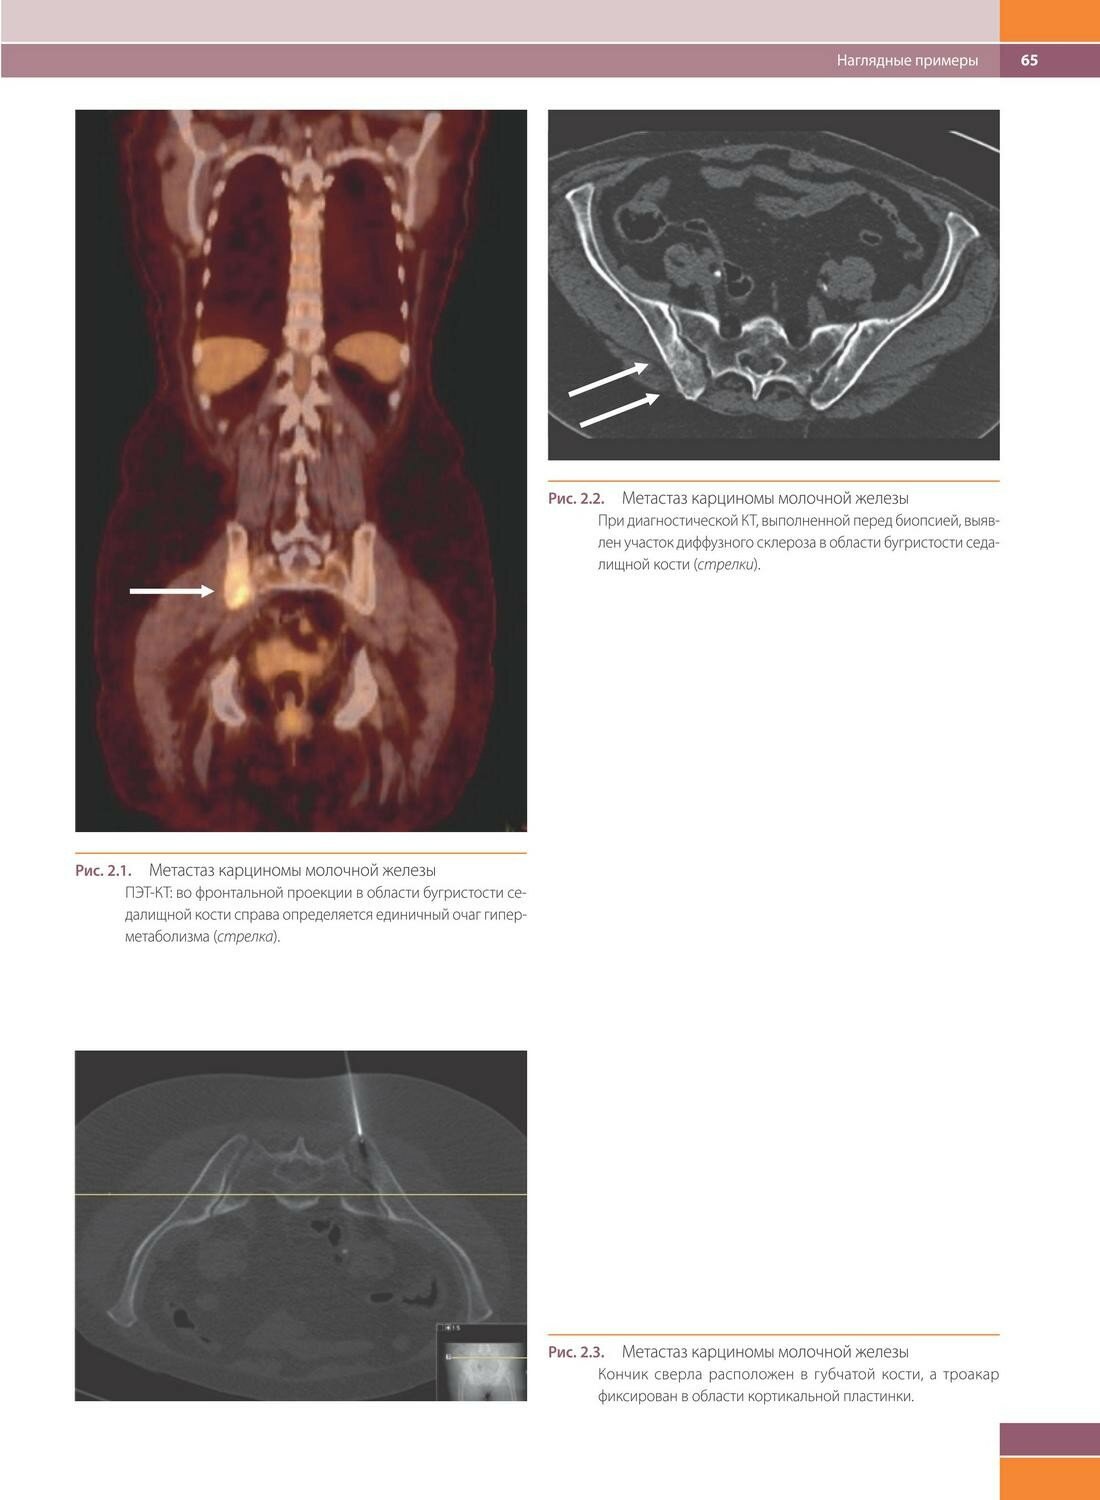

Тонкоигольная аспирационная биопсия - сложный раздел цитологической диагностики, требующий слаженной последовательной командной работы. Настоящее издание вмещает информацию о значении каждого из этапов этого исследования: особенности получения материала и пробоподготовки, сведения о преаналитическом этапе работы с цитологическим материалом, возможностях проведения ТАБ с использованием современных визуализирующих методов диагностики. Книга дает панорамное представление о цитологической диагностике опухолевой и неопухолевой патологии различных органов и тка ней у взрослых и де тей. Отражены современные подходы в интерпретации биопсийного материала анатомических облас тей, вызывающих наибольшие сложности: опухоли головы и шеи, молочной железы, кожи, кос тей, мягких тка ней и внутренних органов. Уникальными представляются главы, посвященные патологии паращитовидных желез, глазницы и придатков глаза, селезенки. Детально изложены особенности интерпретации материала, полученного при ТАБ лимфатических узлов. Отдельные нозологии или их группы рассматриваются с позиций ключевых признаков, дифференциального диагноза и роли дополнительных методов для постановки диагноза. В каждом разделе представлены как типичные, так и редкие нозологии, а богатый иллюстративный материал сопровождается детальным описанием.